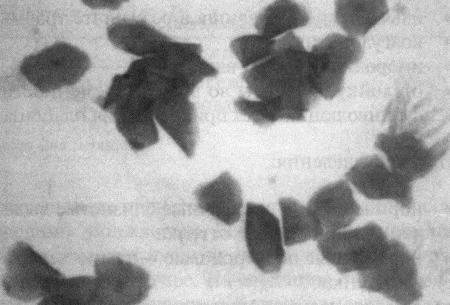

О повышении концентрации эстрогенов можно судить по таким изменениям, как гиперплазия и гипертрофия вагинального эпителия, ороговение и эксфолиация его клеток. Вагинальная цитология позволяет выявить характерные изменения, служащие индикатором активности этого гормона. На стадиях цикла, протекающих на фоне минимальной эстрогенной активности (анэструс, метэструс, препубертатный период), в вагинальных выделениях у сук преобладают парабазальные клетки (фиг 3.1), которые имеют округлые очертания и низкий объем цитоплазмы по отношению к ядру. Под влиянием эстрогенов развивается гипертрофия эпителиальных клеток влагалища, затрагивающая мелкие промежуточные клетки (они крупнее парабазальных, с округлыми очертаниями и относительно более высоким соотношением ядра к цитоплазме; фиг. 3.1–3.3), крупные промежуточные клетки (полигональные клетки с неповрежденным ядром; фиг. 3.3) и поверхностные клетки (сходные с крупными промежуточными клетками, но, как правило, безъядерные или с пикнотичным ядром; фиг. 3.4). Число поверхностных ороговевших безъядерных клеток возрастает в фазе проэструса, сохраняется постоянным в течение эструса (фиг. 3.4) и резко уменьшается к моменту его окончания. Стремительное сокращение (более чем на 20 %) количества этих клеток свидетельствует о наступлении первого дня метэструса (фиг. 3.2). Характерно, что к этому моменту вагинальные выделения просветляются и уже не содержат ни органических остатков, ни окрашенной слизи. Повышенное содержание лейкоцитов может указывать на наличие инфекции, а присутствие аномальных клеток — на опухолевый процесс. Повышенное содержание нейтрофилов, наблюдающееся в начале метэструса (фиг. 3.1 и 3.5), считается нормой и не является признаком патогенной инфекции.

Фиг. 3.2.

В мазке вагинальных выделений у суки во второй день метэструса преобладают мелкие промежуточные клетки, обнаруживается небольшое количество парабазальных клеток (окрашивание мазка модифицированным Schorr's trichrome) (см. Приложение)